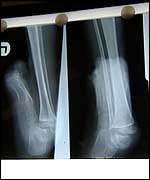

ARTA'S HOPE IN BRISTOL Five-year-old Albanian girl Arta Gjini is in Bristol for life-changing surgery. Her crucial operations will take place at the renowned Frenchay hospital in Bristol. This is all thanks to some kind surgeons and a Somerset charity. Injuries | | X-rays show one foot is bent double, the other formed into a club. |

On Tuesday 24 September surgeons performed Arta's first operation. Over five hours, they cut her left foot away from her shin and lowered it to a right angle. "We’ve managed to get her foot down into a much better position," says surgeon Alan Kay. GratefulMaria Bardhi is accompanying Arta from Rubik as her translator and guardian. She says, "We are lucky we have such good care for Arta." She keeps Arta’s family and friends in Albania regularly posted. Albanian Mayor Gjavolin Prenga is also taking a personal interest. He says, "We want to thank the people of Somerset and the staff at Frenchay and everyone else who’s supported Arta and her family." "Mother Teresa, who was Albanian, used to say she aimed to help the poorest of the poor." "That’s just what the people in Somerset and Bristol are doing." |